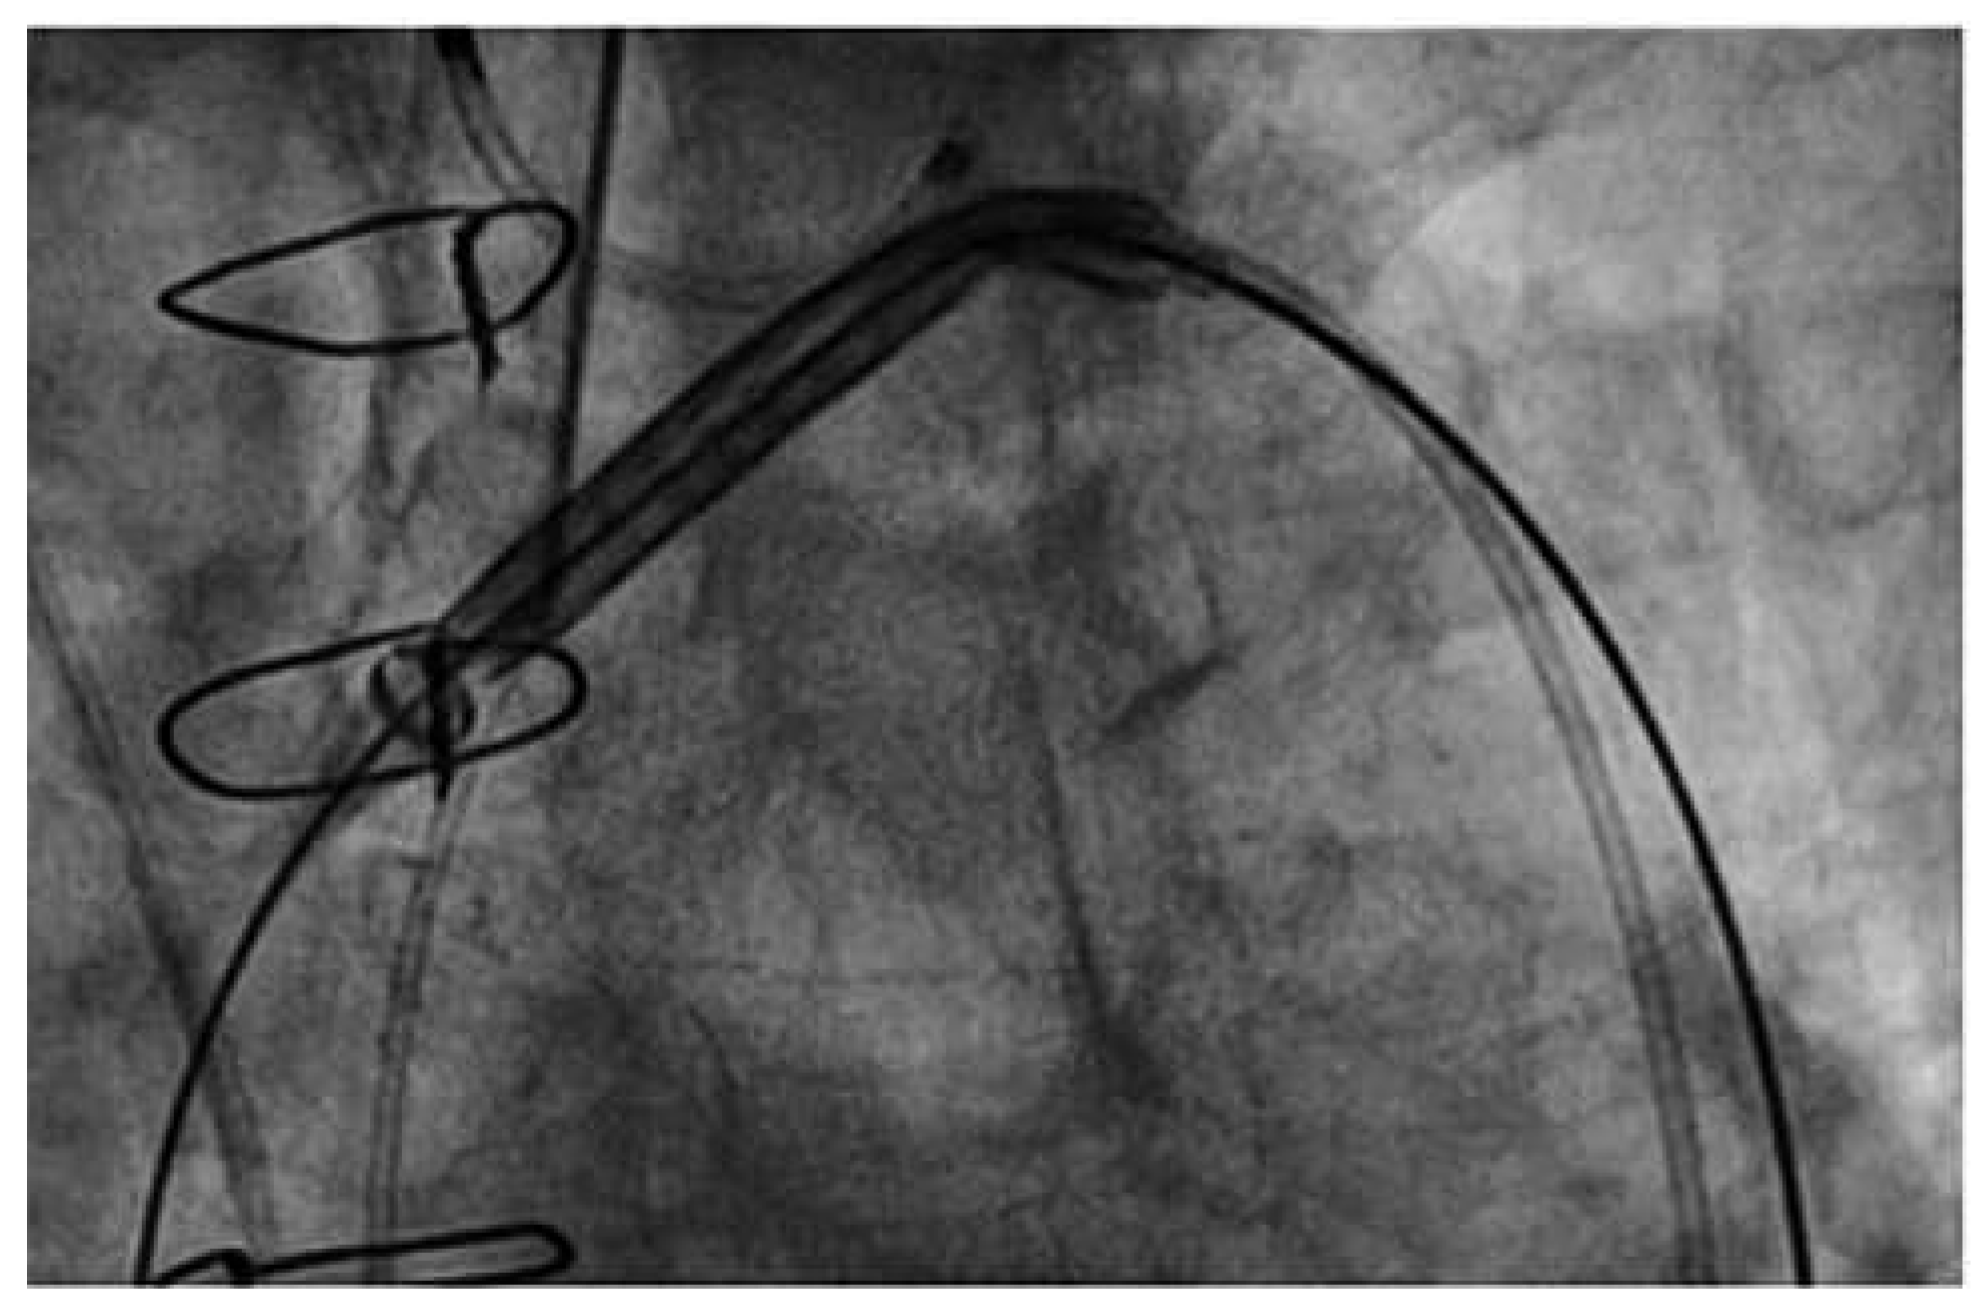

The Claret CE Pro™ device (Claret Medical Inc., Santa Rosa, CA, USA) is introduced via right radial or brachial access. It contains one filter basket to be deployed in the brachiocephalic trunk, and allows introduction of a standard filter wire to the left carotid artery [17]. The system consists of a 6 French sheath, a delivery system and the brachiocephalic filter (Figure 4). The first generation device was modified in order to allow introduction over a 0.014’’ guidewire and by modifying the bend of the distal steerable tip for antegrade probing of the left carotid artery. After deployment of the proximal filter in the brachiocephalic trunk, the distal tip of the delivery system is advanced to the aortic arch and positioned in a way to allow placement of the distal filter in the left carotid artery (Figure 5 and Figure 6).

Figure 6. Claret CE Pro. No interference of the Claret CE Pro™ device with the prosthetic valve delivery system.